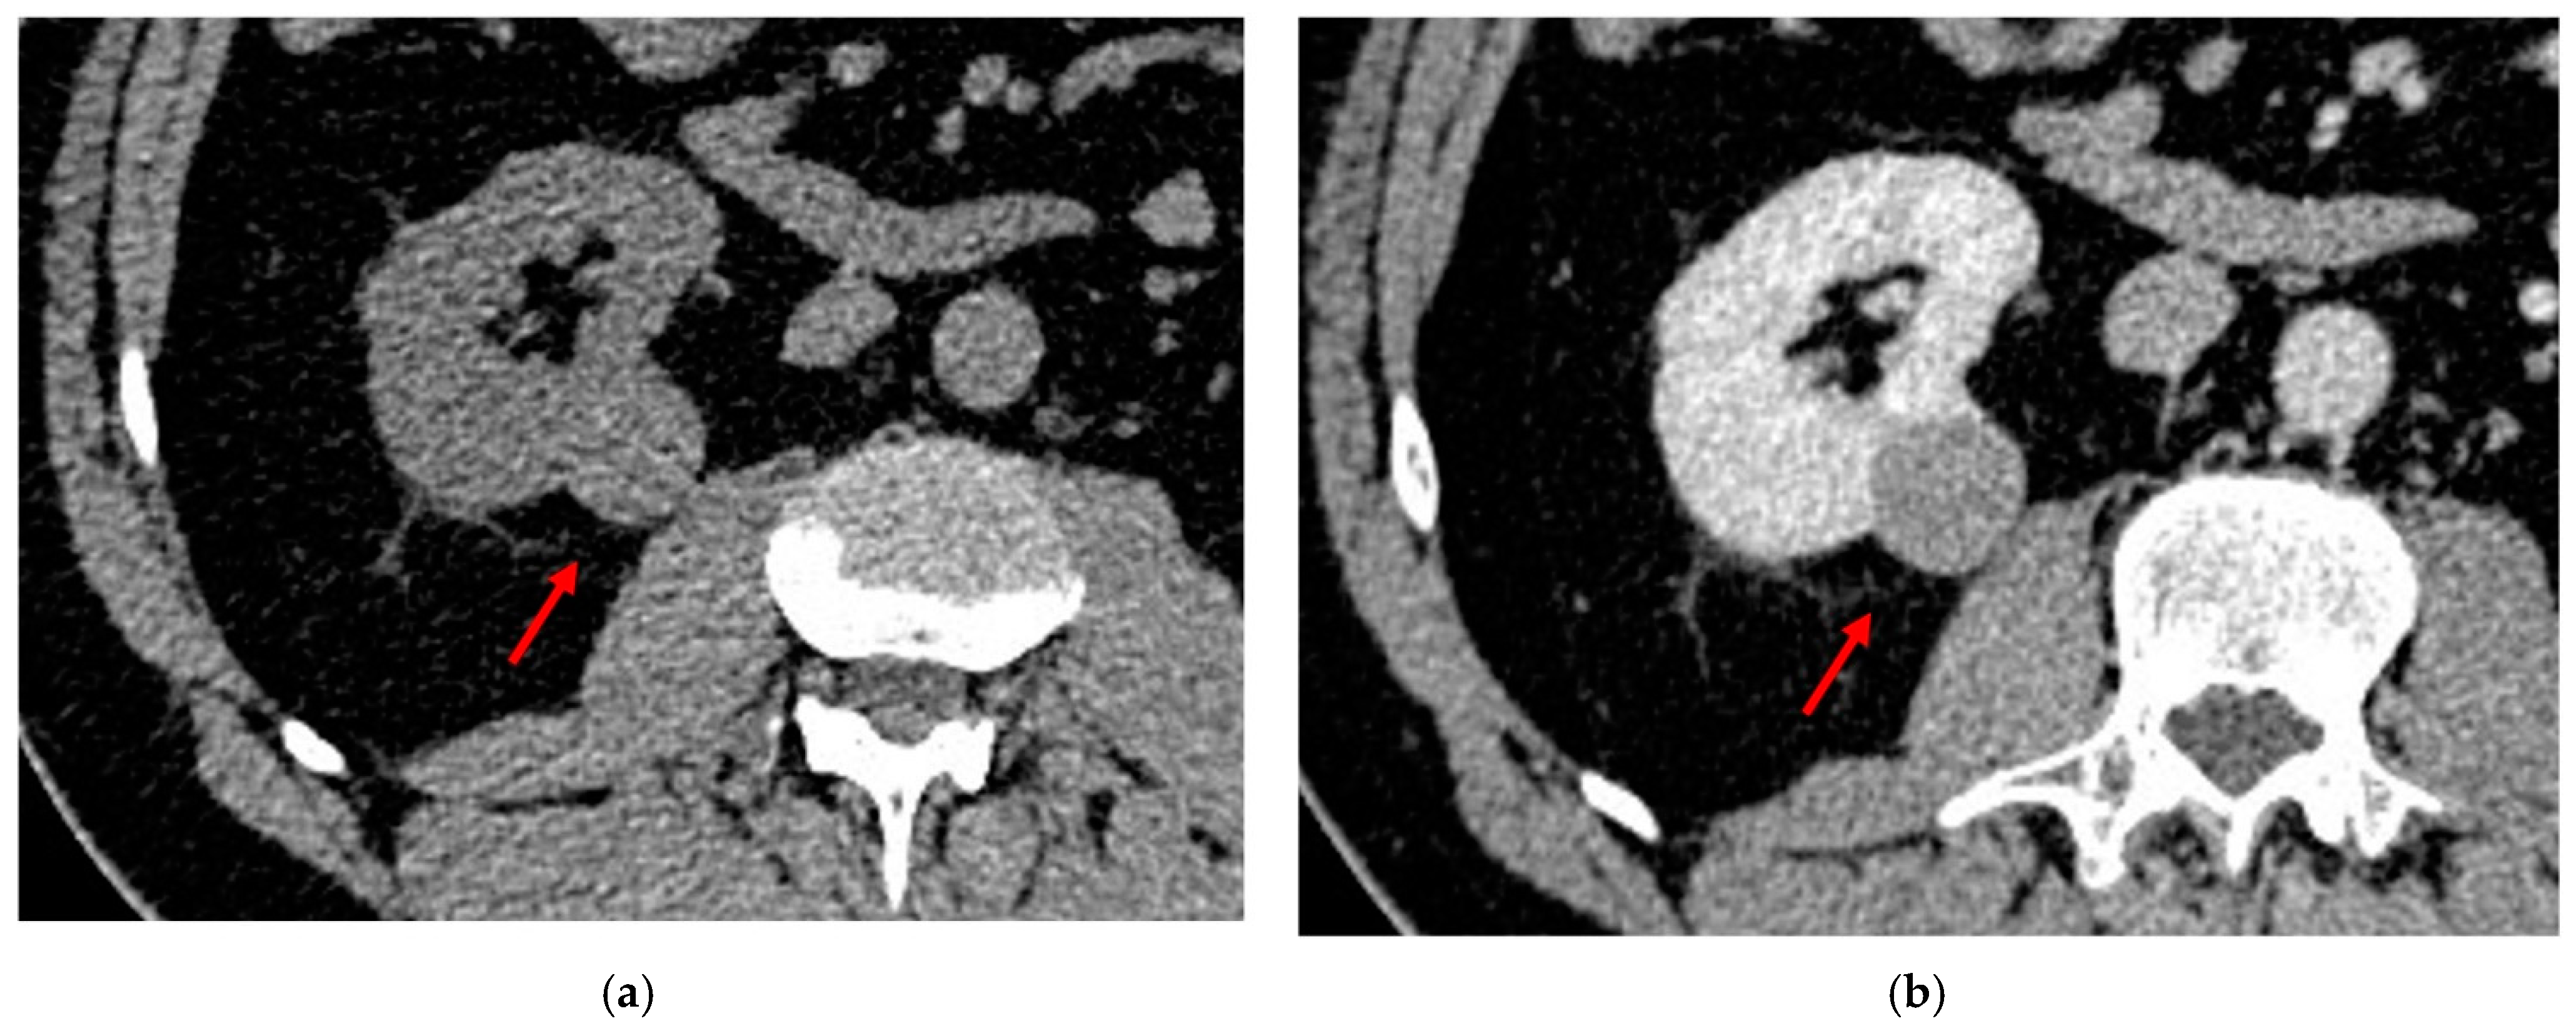

3.4. Urothelial Renal Carcinoma